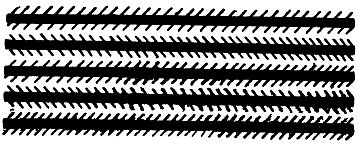

Для испытания глаз на астигматизм врачи-окулисты часто применяют специальную таблицу (рис. 10), где двенадцать кружков имеют штриховку равной толщины через одинаковые интервалы.

Рис. 10. Фигура для определения степени и меры астигматизма глаза.

Глаз, обладающий астигматизмом, увидит линии одного или нескольких кружков более черными. Направление этих более черных линий позволяет сделать вывод о характере астигматизма глаза.